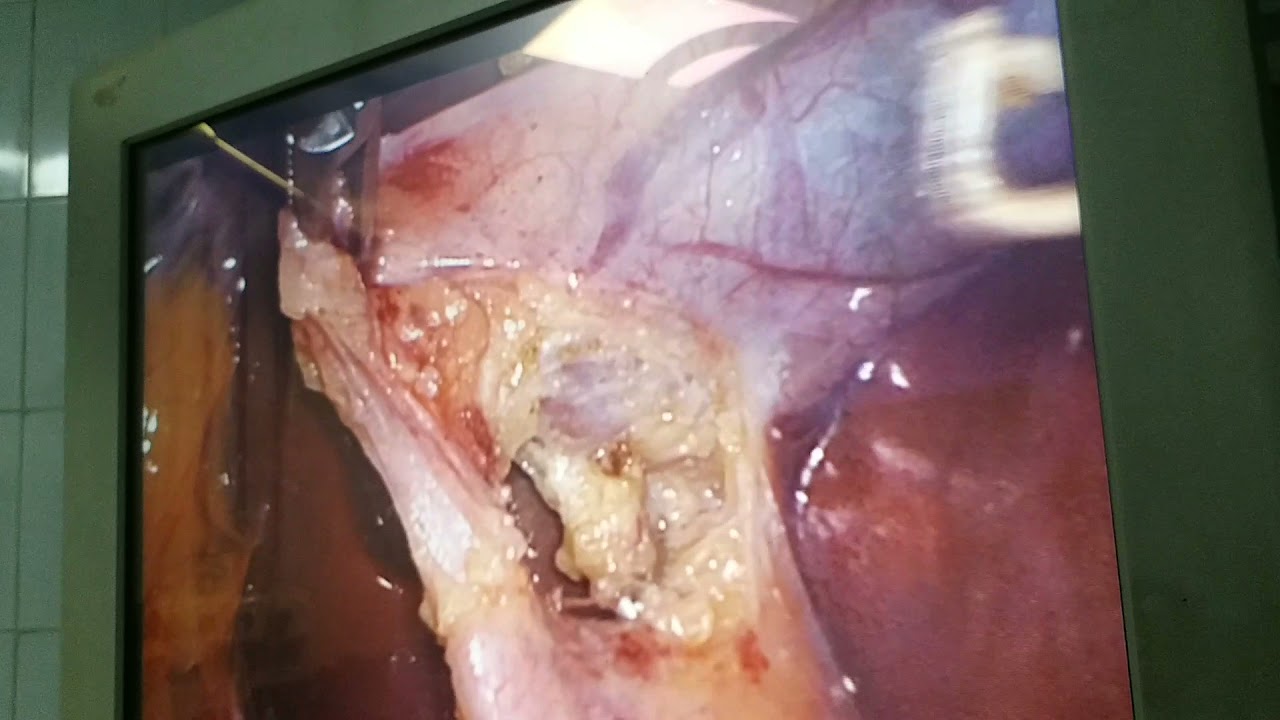

Hook dissection in laparoscopic cholecystectomy @drvikrantsinghchandail